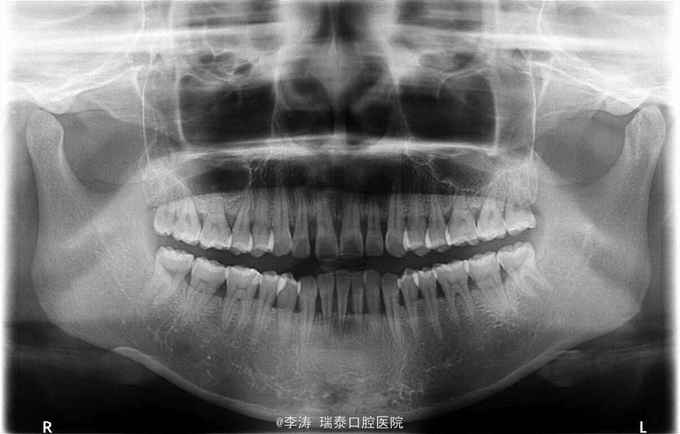

前牙间隙较大,全口牙龈红肿探诊出血,x线片,全口牙齿牙槽骨吸收至根中三分之一,牙周探诊示牙周袋深度均大于5mm